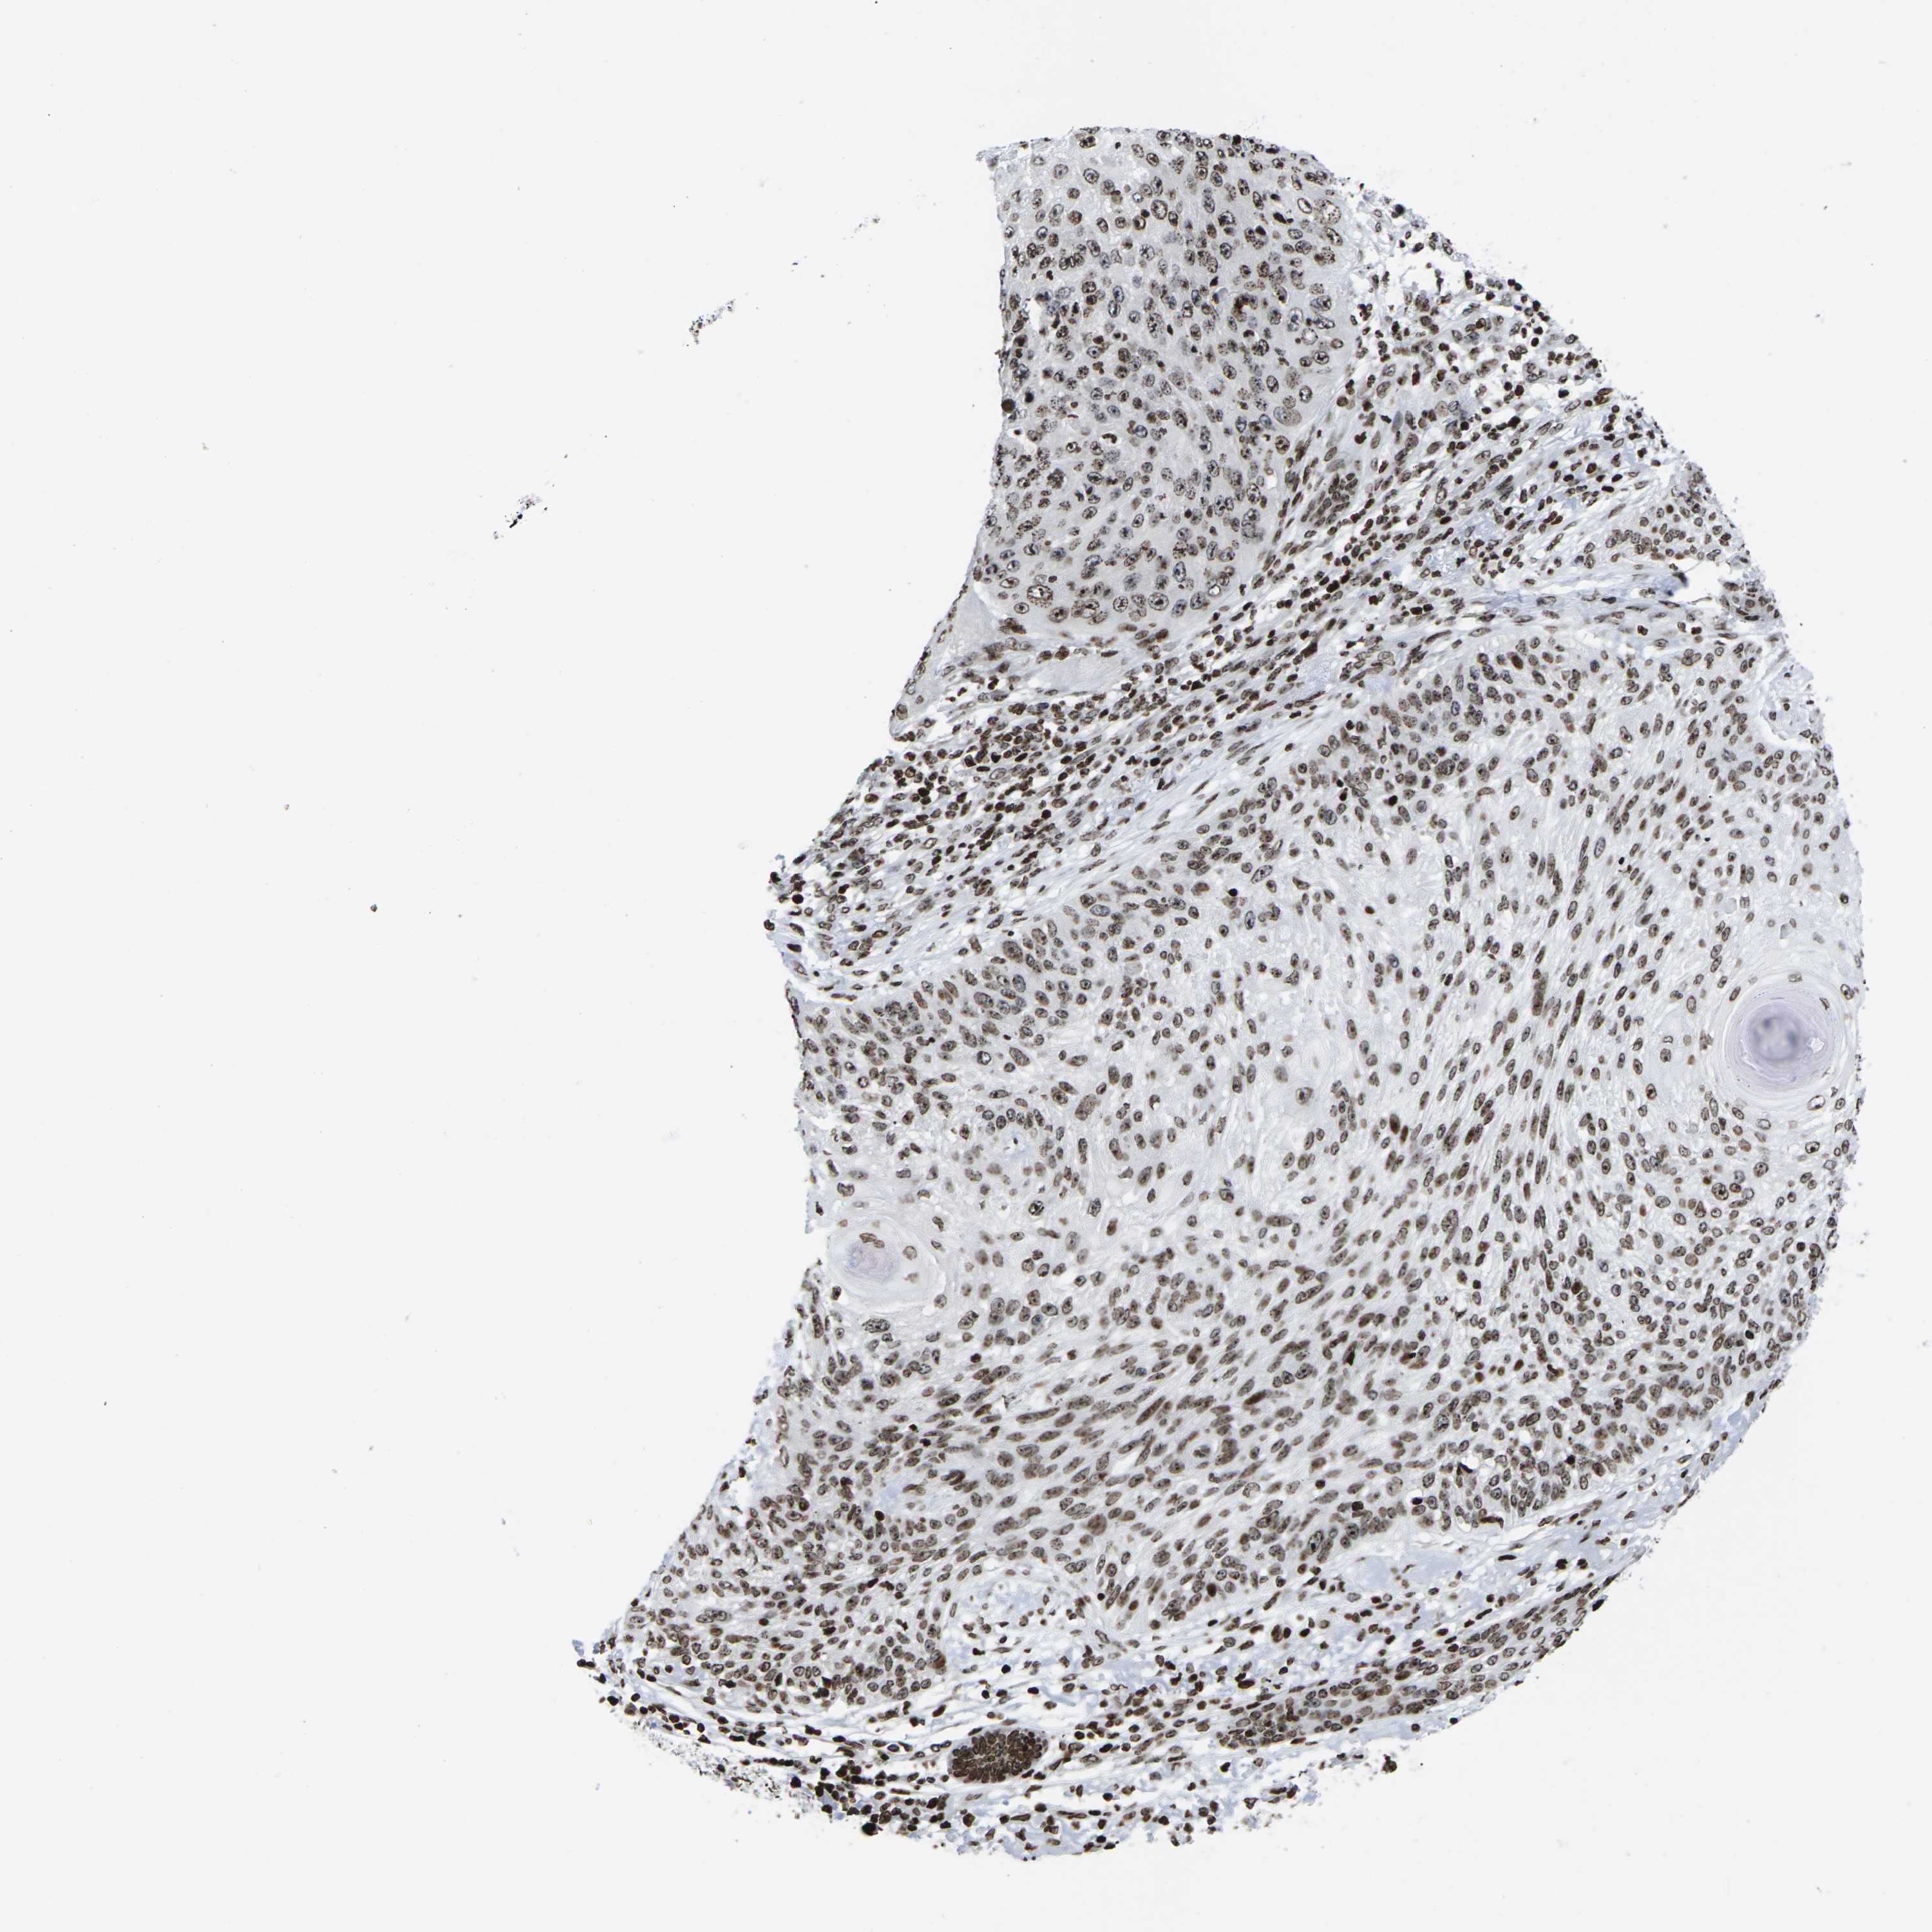

SKIN CANCER - Protein expressioni

A mouse-over function shows sample information and annotation data. Click on an image to view it in a full screen mode. Samples can be filtered based on level of antibody staining by selecting one or several of the following categories: high, medium, low and not detected. The assay and annotation is described here.

Antibody stainingi

Antibody staining in the annotated cell types in the current human tissue is reported as not detected, low, medium, or high, based on conventional immunohistochemistry profiling in selected tissues. This score is based on the combination of the staining intensity and fraction of stained cells.

Each image is clickable and will lead to virtual microscopy that enables deeper exploration of all samples and also displays staining intensity scores, fraction scores and subcellular localization as well as patient and tissue information for each sample.

Antibody HPA055907

Antibody CAB011506

Staining

High

Medium

Low

Not detected

Intensity

Strong

Moderate

Weak

Negative

Quantity

>75%

75%-25%

<25%

None

Location

Nuclear

Cytoplasmic/membranous

Cytoplasmic/membranous,nuclear

Basal cell carcinoma

Squamous cell carcinoma, NOS

Squamous cell carcinoma, metastatic, NOS

Squamous cell carcinoma in situ, NOS

Adnexal tumor, benign